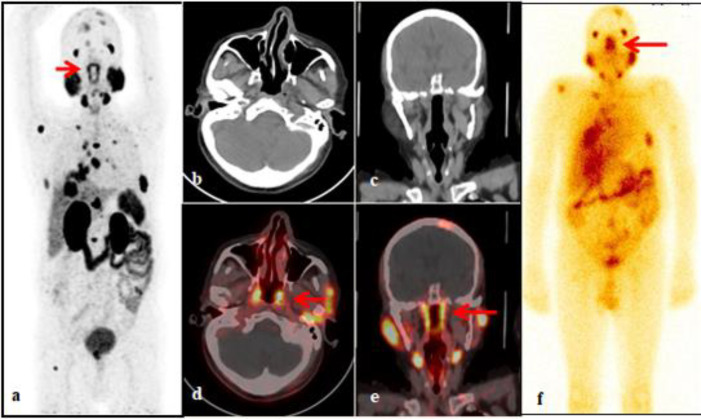

68Ga-PSMA PET/CT has been routinely utilized in patients with intermediate to high-risk category prostate carcinoma for staging, biochemical recurrence and before planning the PSMA radioligand therapy (RLT). 177Lu-PSMA RLT has also been approved by FDA as a novel treatment modality in metastatic carcinoma prostate patients who have failed to other lines of treatment. The non-target organs like salivary and lacrimal glands have shown to have high physiological PSMA uptake on PSMA PET/CT. Recently, strong uptake of PSMA ligand has also been noted in the dorsal wall of the nasopharynx in the region of torus tubarius on PSMA PET/CT, which has led to the identification of new pair of salivary gland structures called "tubarial salivary glands". The clinical significance of these distinct anatomical structures lies in the fact these structures might be involved in a variety of immune related, inflammatory disorders, malignancies and could be a probable organ at risk during radiotherapy in case of head and neck malignancies, causing adverse effects to the patient.